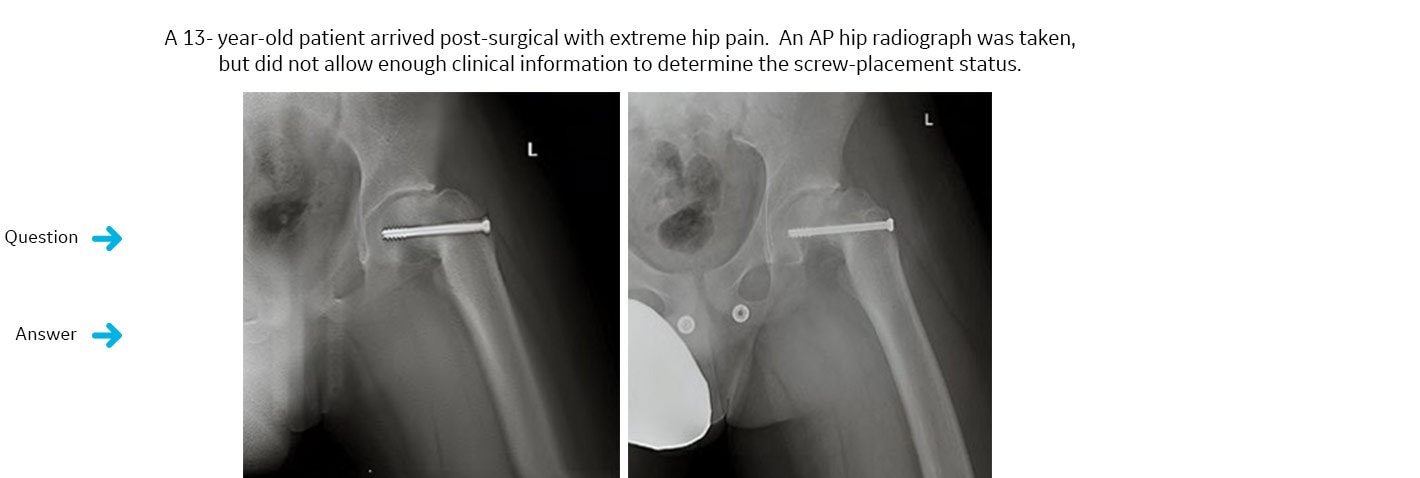

İmplante edilen vida, kalça eklemi bölgesine yerleştirildi mi?

VolumeRAD tetkiki istendi. VolumeRAD üst üste binen yapıların kaldırılmasını sağlayıp güvenilir bir tanı konulmasına yardımcı oldu.Kesin yanıt: Hayır.

VolumeRAD verilerinden alınan tek bir kesit, implante edilen vidanın eklem bölgesine yerleşmediğini ortaya koydu. Hasta ikincil bir ameliyat geçirdi ve implantın düzgün şekilde yerleştirildiği doğrulandı.